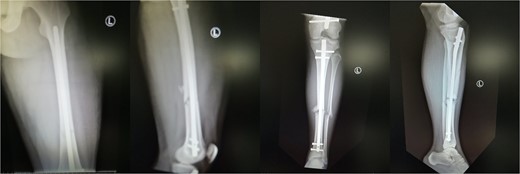

Upon suspicion, the patient should be transferred to the operating room, where either selected or extended fasciotomies should be performed. Upon early diagnosis and emergent reaction, the prognosis of WLCS is excellent with 95% of patients reporting no significant deficit [7,9]. On the other hand. Fitzgerald et al. [10] reported that 81% of patients undergoing fasciotomies develop long-term complications, but this should not deter surgeons from performing fasciotomies when deemed necessary. In the setting though of a delayed diagnosis, like our second case, surgical fasciotomy is no longer effective and might lead to serious complications, such as infection and limb amputation [11]. Our review suggests that the 29.4% of the patients who develop WLCS post-surgery achieved full recovery. 5.9 and 64.7% of the patients achieved no and partial recovery, respectively (Fig. 4).